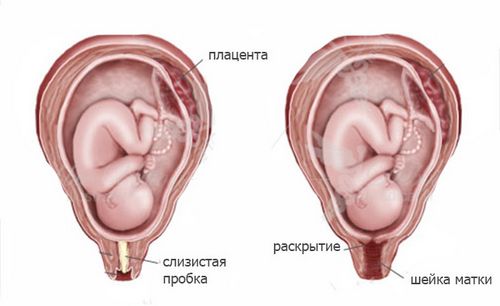

Відповідь на питання, як відходять води у вагітних, неоднозначний. Амніотична рідина може виливатися при безпосередньому настанні пологів або на початку сутичок. Ідеальним варіантом вважається прорив плодової оболонки з настанням родової діяльності при розкритті шийки матки на 4 см.

Нерідкі випадки, коли зберігається цілісність плодового міхура при пологах. У такій ситуації води виливаються лише тоді, коли фахівець проколе міхур.

- Амніотична рідина розділяється на дві частини: передні і задні води. З початком пологів виливається перша частина вод, тим самим допомагаючи малюку просунутися до шийки матки. Друга частина виходить разом з появою дитини на світ. Цей варіант найбільш сприятливий, так як задні води забезпечують краще проходження дитини по родових шляхах.